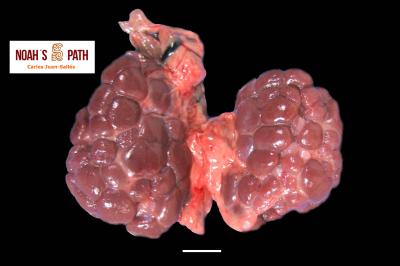

El examen post mortem ofrece una oportunidad única de acceso a todos los tejidos del paciente para diagnóstico de las causas de enfermedad y muerte, y por lo tanto es esencial para medicina preventiva y curativa en grupos de animales, seguimiento de casos, estudios sobre enfermedades, control de zoonosis, medicina de la conservación, y patología forense. En Noah's Path pensamos que un examen post mortem de este tipo de fauna debería ser realizado siempre que sea posible por patólogas/os especializadas/os con el fin de obtener el máximo de información y obtener las muestras más adecuadas.